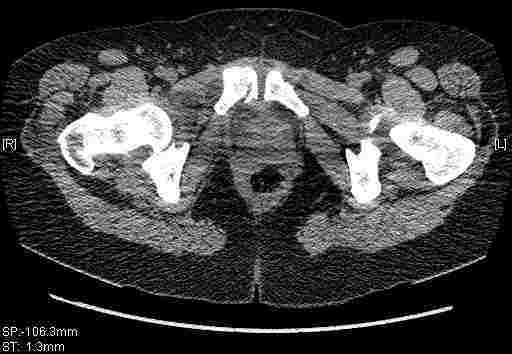

Женщина,58 лет, после ДТП 6 суток. Первично повреждение расценено как переломы ветвей лонной кости. После подтверждения повреждения вертлужной впадины,как чаще всего случается, вопрос встал о тактике. БОльшинство за консерватиное лечение.К сожалению кт у нас "во время" сломался. Прилагаю стандартные снимки вертлужки. У меня следующие вопросы к коллегам:1. Правильно ли рассценивать это повреждение как Т-образный перелом вертлужнй впадины?2. Можно ли добиться анатомической репозиции поверхности вертлужной впадины скелетным вытяжением в данном случае, если нет, что будет этому препятствовать?3. Если смещение останется таким как сейчас, через какое время появится необходимость эндопротезирования (по вашему опыту)?Спасибо.

Удалось сегодня вывести пациентку в соседнюю больницу, где есть кт. Срезы сделаны только горизонтальные.

|